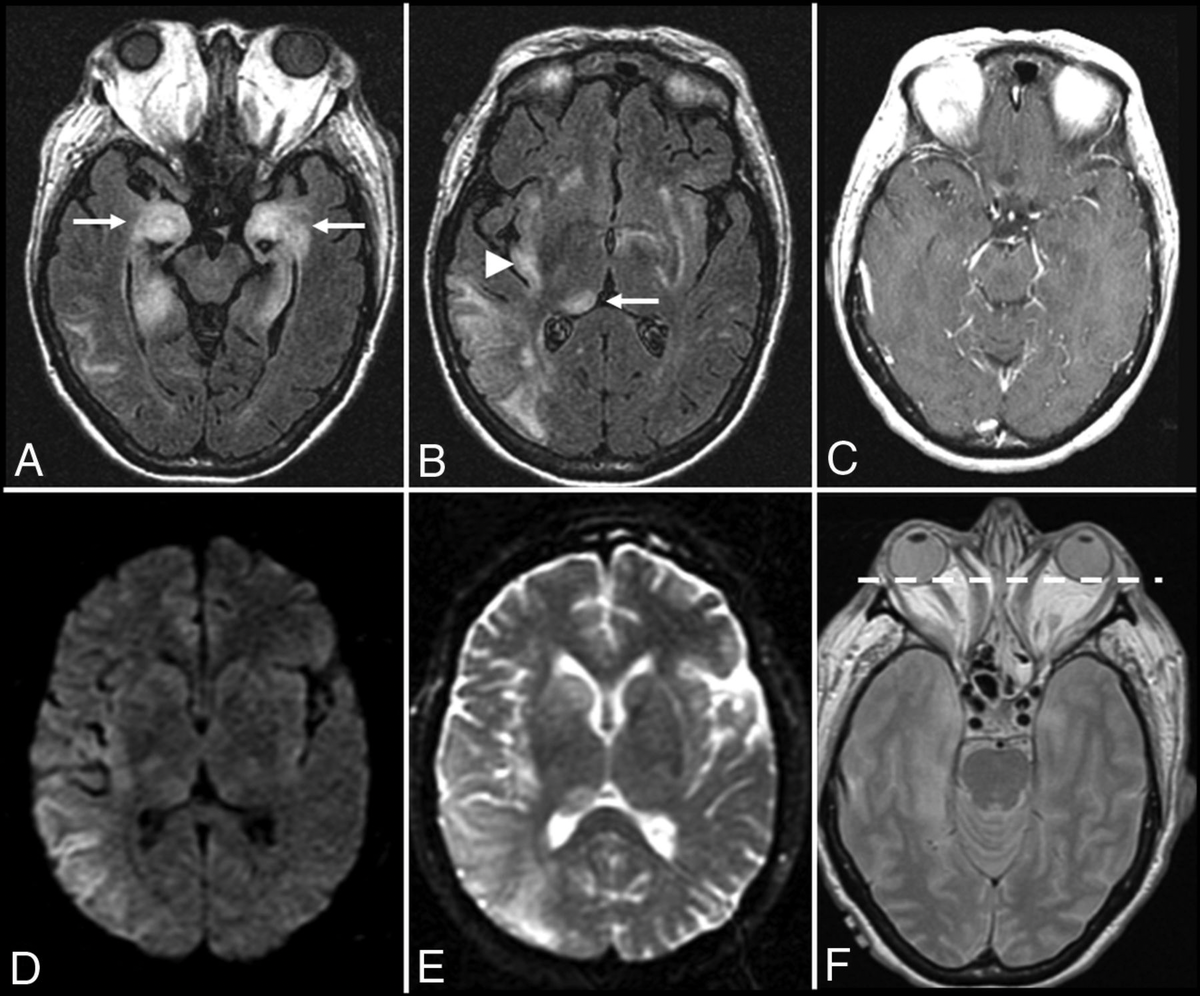

https://www.ajnr.org/content/38/6/1070?ijkey=f1b602adce673f24116fe740e0aa77d8b01e453c&keytype2=tf_ipsecsha